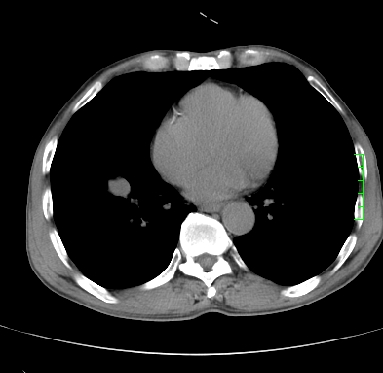

m,73y。膝关节疼痛伴双下肢水肿。入院常规胸片发现结节灶。增强为静脉期。

浅分叶、棘突,考虑右下肺周围型肺癌

考虑周围型肺癌  ,双上肺结核。

肿块周围可见局限性气肿,考虑肺癌可能性大。双肺上叶继发型肺结核。

指套征,强化明显,近侧肺组织局限性肺气肿,考虑支气管类癌,慢支、肺气肿、双上陈旧性tb、冠脉钙化。

1)考虑右肺下叶周围型肺癌。2)右肺上叶及左肺感染性病变(结核可能)。3)肺气肿。4)冠状动脉钙化。